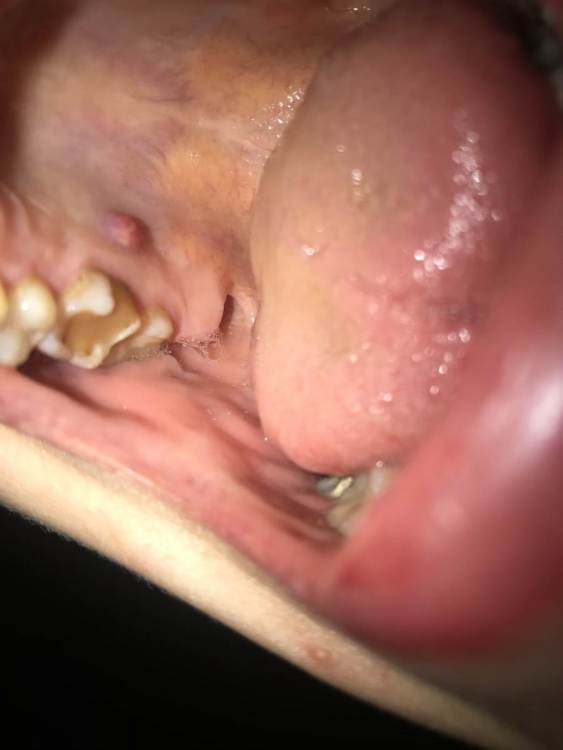

Мария-33 Опубликовано 13 июня, 2021 Поделиться Опубликовано 13 июня, 2021 Здравствуйте! Появилась шишка около месяца назад , на верхнем небе , на что это похоже, подскажите пожалуйста? Не болит , не кровоточит. На данный момент кажется, что изначально она была помягче и поменьше. Ссылка на комментарий

Doc Опубликовано 13 июня, 2021 Поделиться Опубликовано 13 июня, 2021 Это повод сходить к стоматологу, сделать КТ и выяснить, подлежит зуб еще лечению или уже совсем нет. 2 Ссылка на комментарий